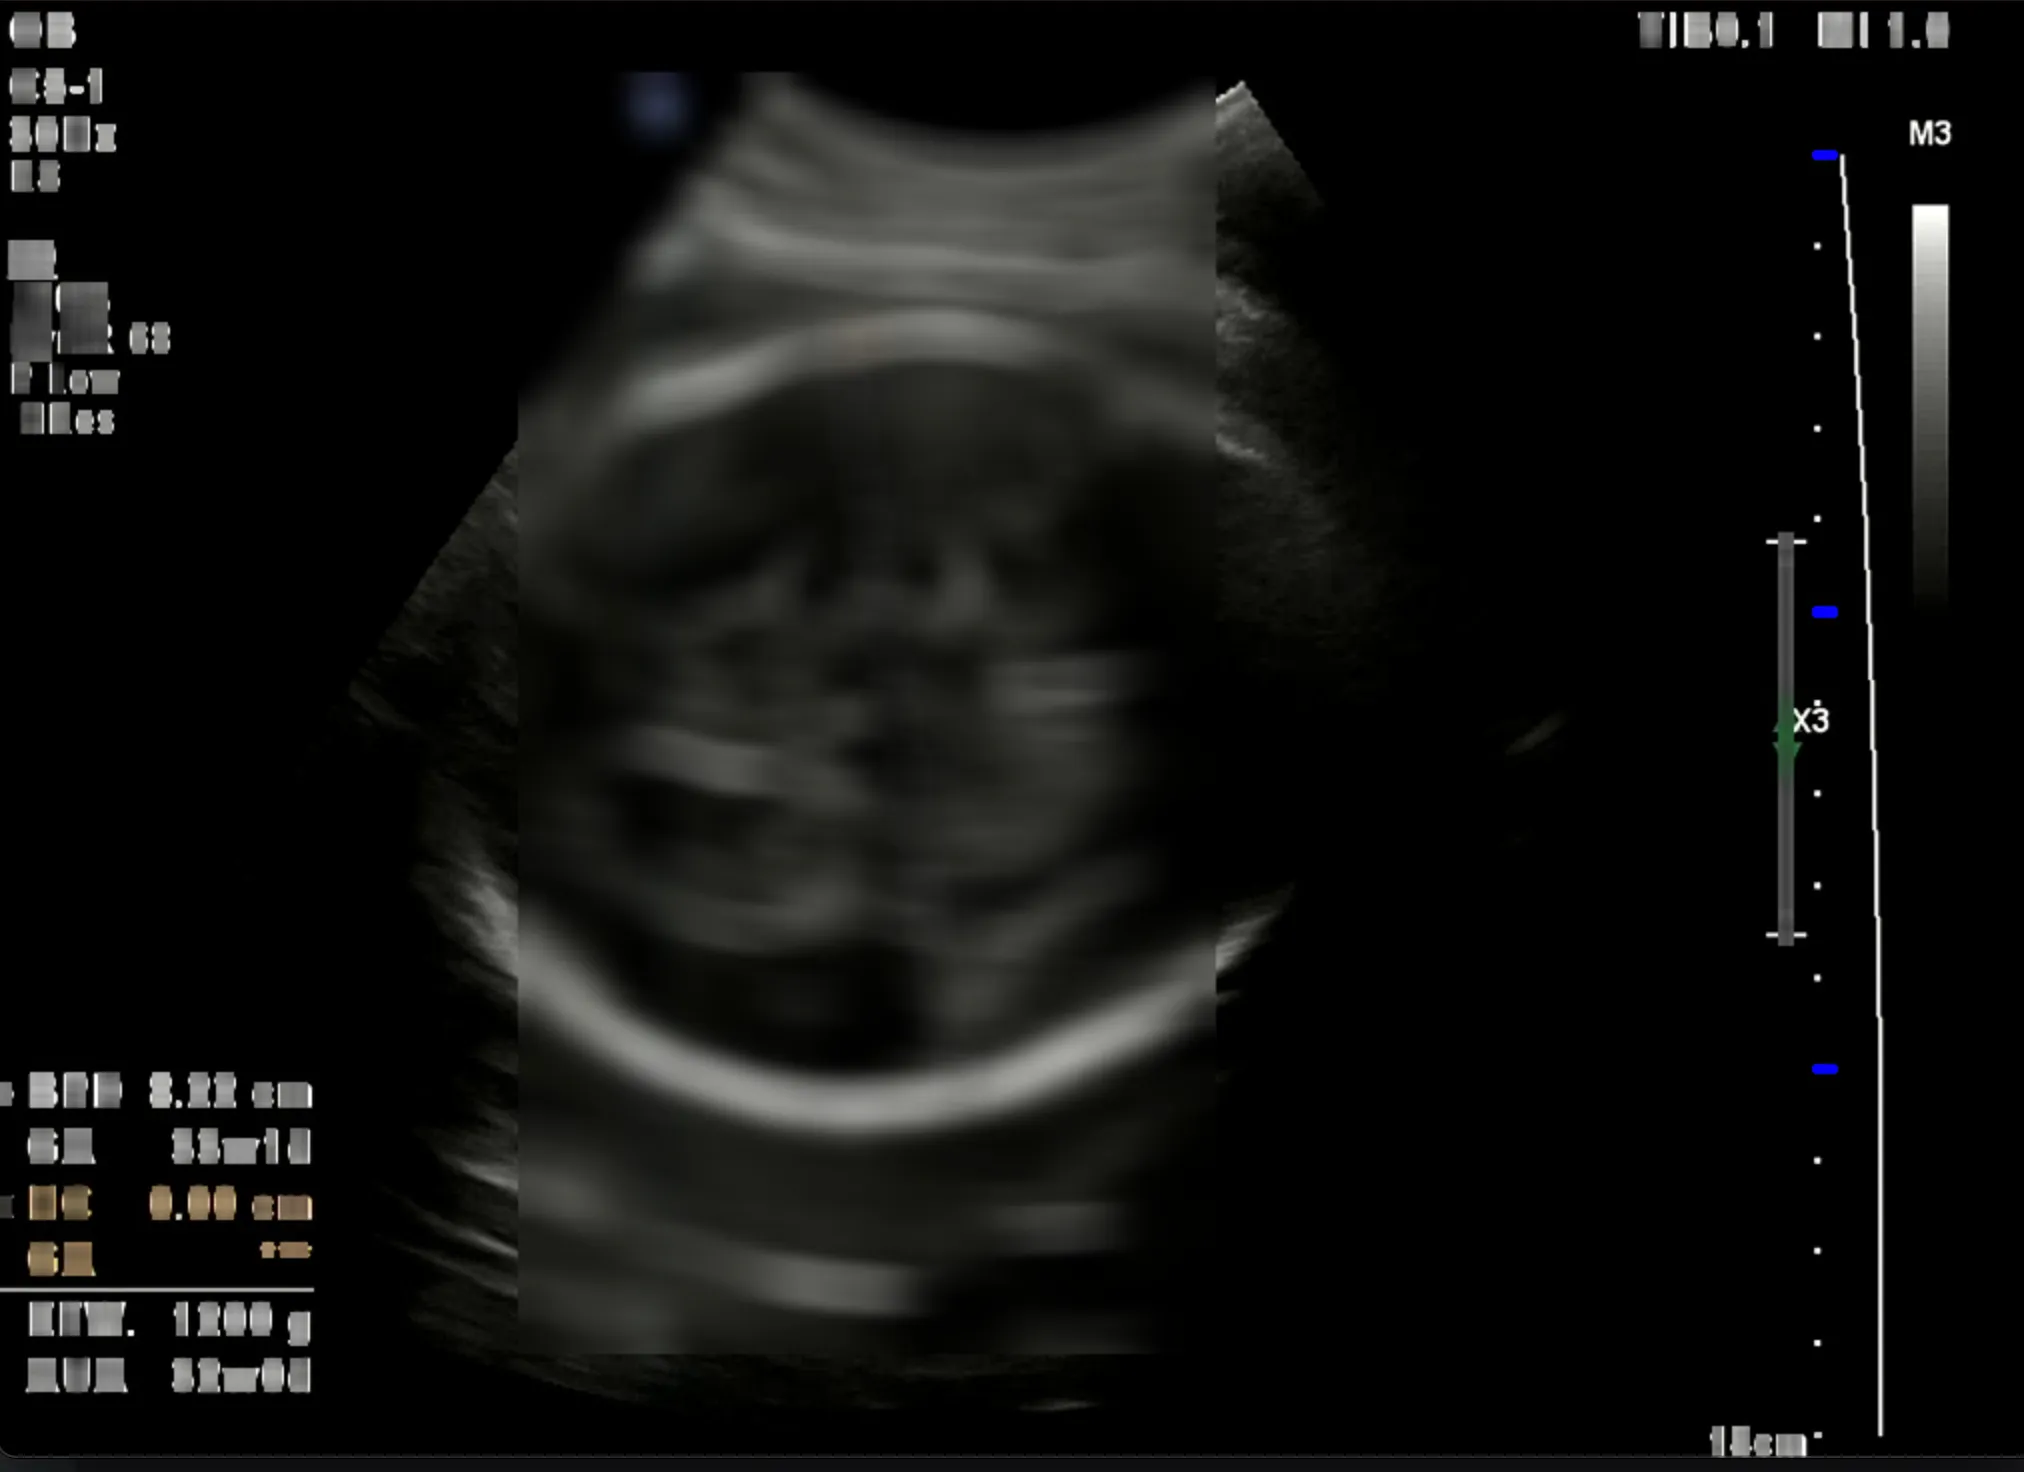

초음파 진단 장비마다 스케일바의 위치가 정말 다양했다. 좌측 혹은 우측이었다. 우선 스케일바 영역을 찾는 것부터 먼저 진행했다. 이어서 눈금 간격을 측정해서 픽셀 당 거리로 환산했다. 가장 굵은 눈금을 측정하는 것에 집중했다. (파란색으로 강조) 그 이유는 모든 눈금을 측정하려다 보니 온갖 점들이 인식되어 노이즈가 발생헀다. 그래서 파란색 눈금 사이의 픽셀 거리를 구하고 cm 당 픽셀 거리로 계산하여 배율을 구했다. 그런데 이 과정에서 사실 내가 간과한 치명적인 오류가 있었다. 😭 눈금 간격을 무조건 1cm 로 간주했다는 점이다.

첫 번째 사진은 실제로 눈금 간격이 1cm 였다. 하지만 두 번째 사진은 그렇지 않았다. 눈금 간격이 1cm 가 맞다면 왼쪽 눈금의 전체 길이는 최소한 20cm 가 넘는다. 그런데 실제로 측정된 BPD 는 3.72cm 였다. 여러 이미지를 테스트하면서 픽셀 거리를 어림짐작하여 배율을 구하는 if-else 문을 만들게 되었다. 당장 프로토타입으로는 문제가 없지만 장기적으로는 올바른 판단이 아니라고 생각했다. 방법을 찾고 싶었다. 초음파 이미지를 뚫어지게 쳐다보며..